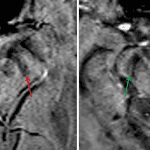

- Absence of the normal “swallow tail” sign

Parkinson disease

Absence of the normal “swallow tail” sign. While this may be artifactual, this appearance can be seen in conjunction with the clinical diagnosis of Parkinson disease.

- Broski SM, Hunt CH, Johnson GB, Morreale RF, Lowe VJ, Peller PJ. Structural and functional imaging in parkinsonian syndromes. Radiographics 2014; 34: 1273-1292.

- Schwarz ST, Afzal M, Morgan PS, Bajaj N, Gowland PA, Auer DP. The ‘swallow tail’ appearance of the healthy nigrosome – a new accurate test of Parkinson’s disease: a case-control and retrospective cross-sectional MRI study at 3T. PLoS One 2014; 9(4): e93814.